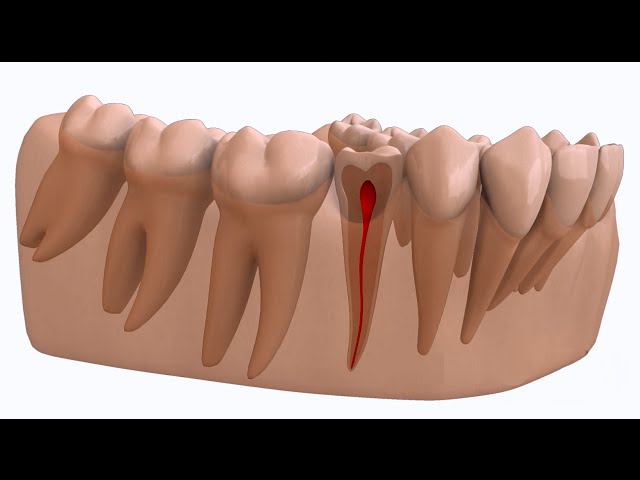

Un abcès dentaire est une infection bactérienne douloureuse qui se forme au niveau de la racine d’une dent ou entre la dent et la gencive. Cela peut survenir lorsque la carie dentaire n’est pas traitée, permettant aux bactéries d’atteindre la pulpe dentaire, où se trouvent les nerfs et les vaisseaux sanguins. L’abcès se développe lorsque le corps réagit à l’infection en envoyant des globules blancs pour combattre les bactéries, créant ainsi une accumulation de pus.

Les origines des abcès dentaires peuvent être variés : une carie dentaire profonde – un traumatisme de la dent – une fracture d’une racine dentaire – une résorption dentaire etc.